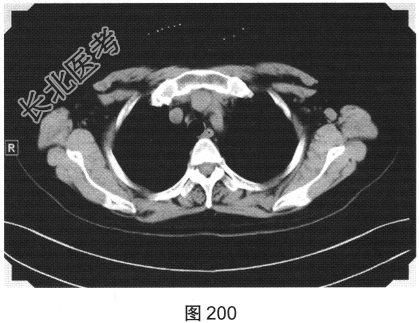

- 简答题4、该患者行颈部淋巴结活检,组织病理学结合免疫组织化学染色,考虑非霍奇金淋巴瘤弥漫大B细胞型。对该患者进一步行胸部、腹部、盆腔增强CT检查,如图200、图201所示。请问患者以上CT检查可见哪些影像异常?